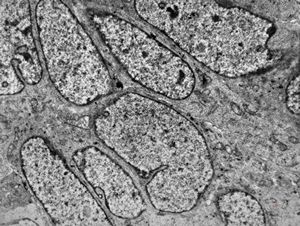

M,22y. | normal bronchial epithelium